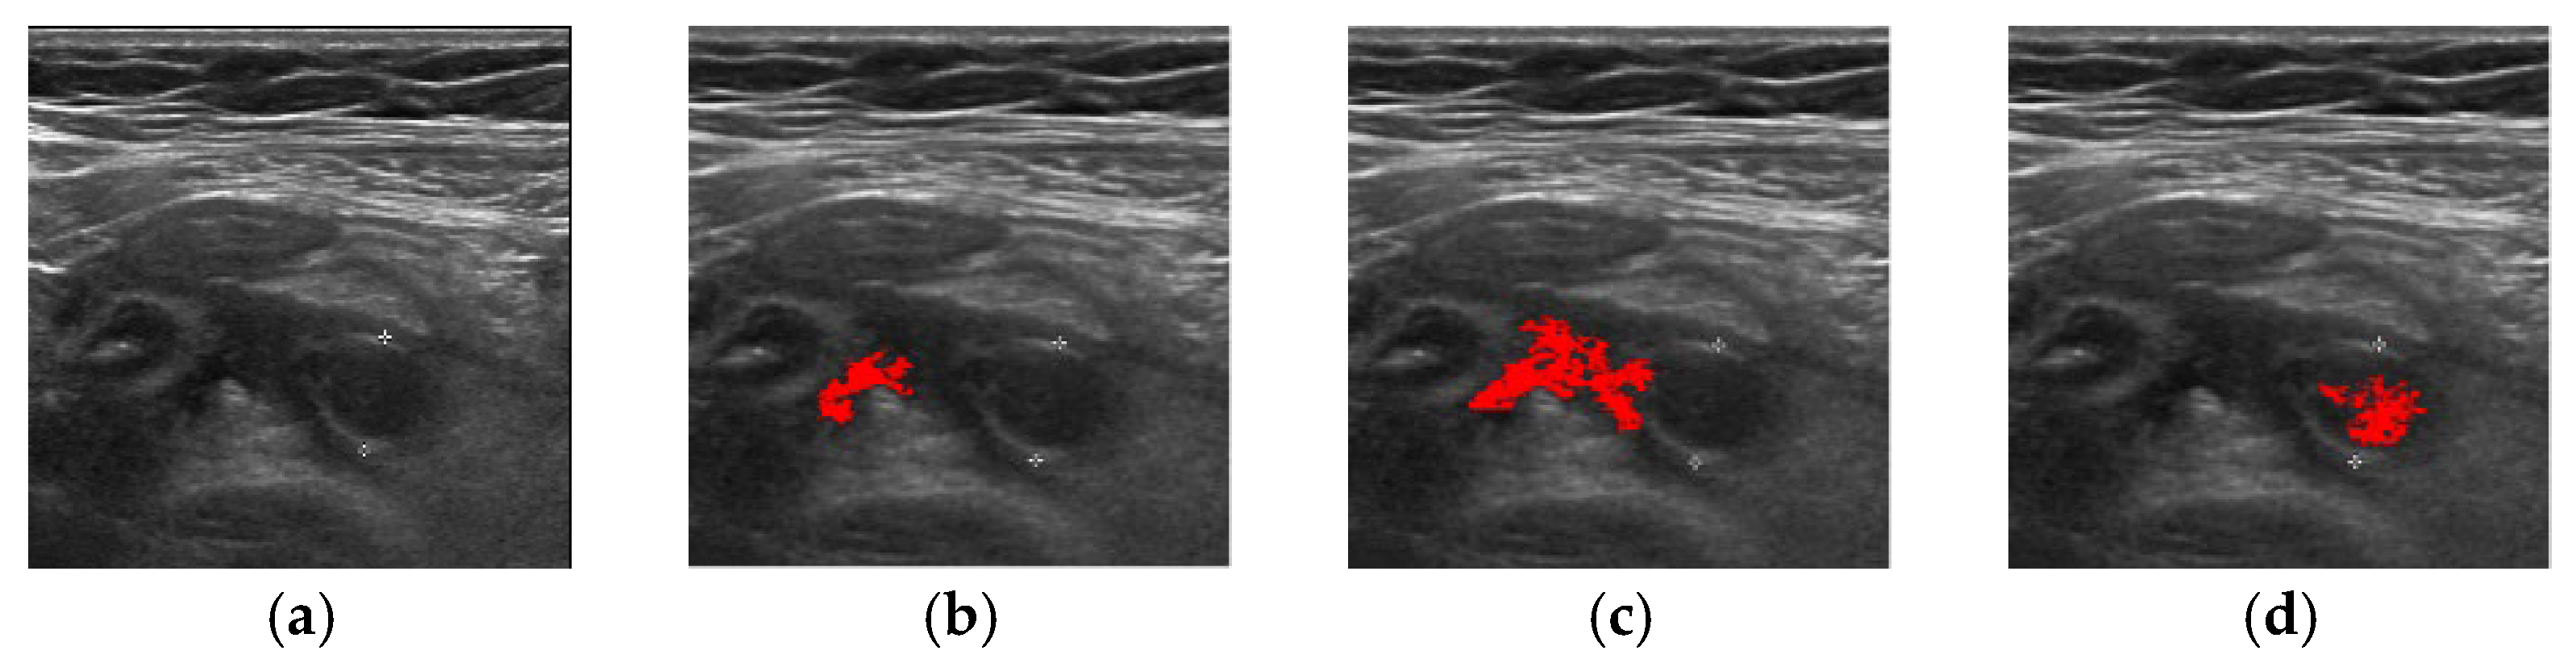

| Method | Successful Images/Total Images |

|---|---|

| FCM | 83/100 |

| ORFCM | 88/100 |

| DFCM | 91/100 |

| DORFCM | 98/100 |

| Accuracy | Precision | Recall | |

|---|---|---|---|

| DORFCM | 84.20% | 83.40% | 85.80% |

| DFCM | 80.80% | 80.90% | 80.20% |